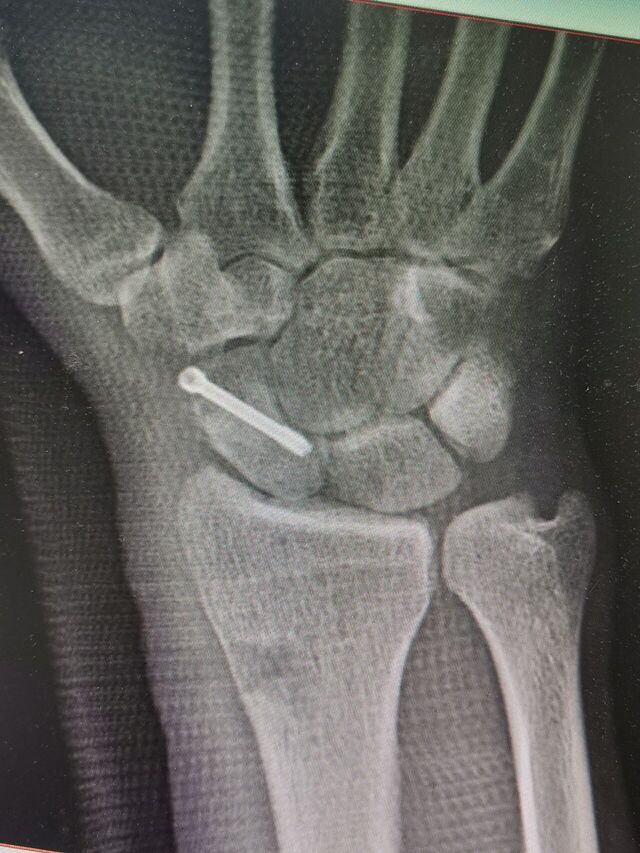

舟骨陈旧骨折,驼背畸形

术中失去对合参照

IMG_20240807_154525.jpg

IMG_20240807_154538.jpg

IMG_20240807_154625.jpg